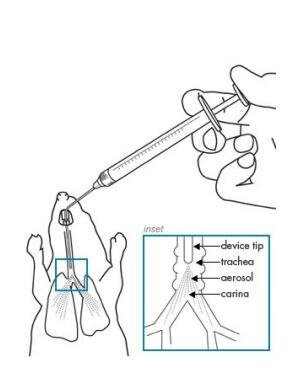

- 麻醉与固定:使用麻醉剂(如10%水合氯醛)使动物进入麻醉状态,仰卧固定于实验台上,颈部去毛后酒精消毒,切开皮肤,逐层暴露气管。

- 药物制备:将博来霉素溶解于生理盐水或PBS中,制备成一定浓度的药液,通常为4-5 mg/kg或15 mg/kg。

- 气管内给药:使用气管插管将药物注入气管,注入后迅速旋转动物,使药物均匀分布于肺组织。例如,将1mL注射器经两气管软骨环间隙朝向心端刺入气管,注入博来霉素(约4~5mg/kg)再向气管内注入~3次,使药物在肺部分布均匀。

气管注射给药

- 术后处理:缝合皮肤,消毒,待动物清醒后常规饲养。造模后需观察动物的体重变化、呼吸状态等指标。